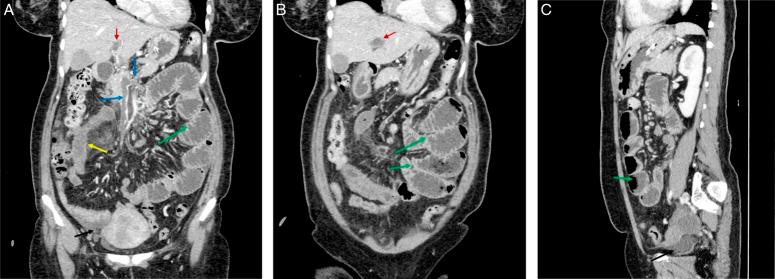

CASE PRESENTATION

A 45-year-old female presented with severe abdominal pain, vomiting, and constipation. Diagnosis revealed PVT-induced intestinal obstruction, an exceptionally rare occurrence in the context of prolonged OCP therapy. The patient's symptoms improved with conservative management, including rivaroxaban, highlighting the crucial role of early intervention.